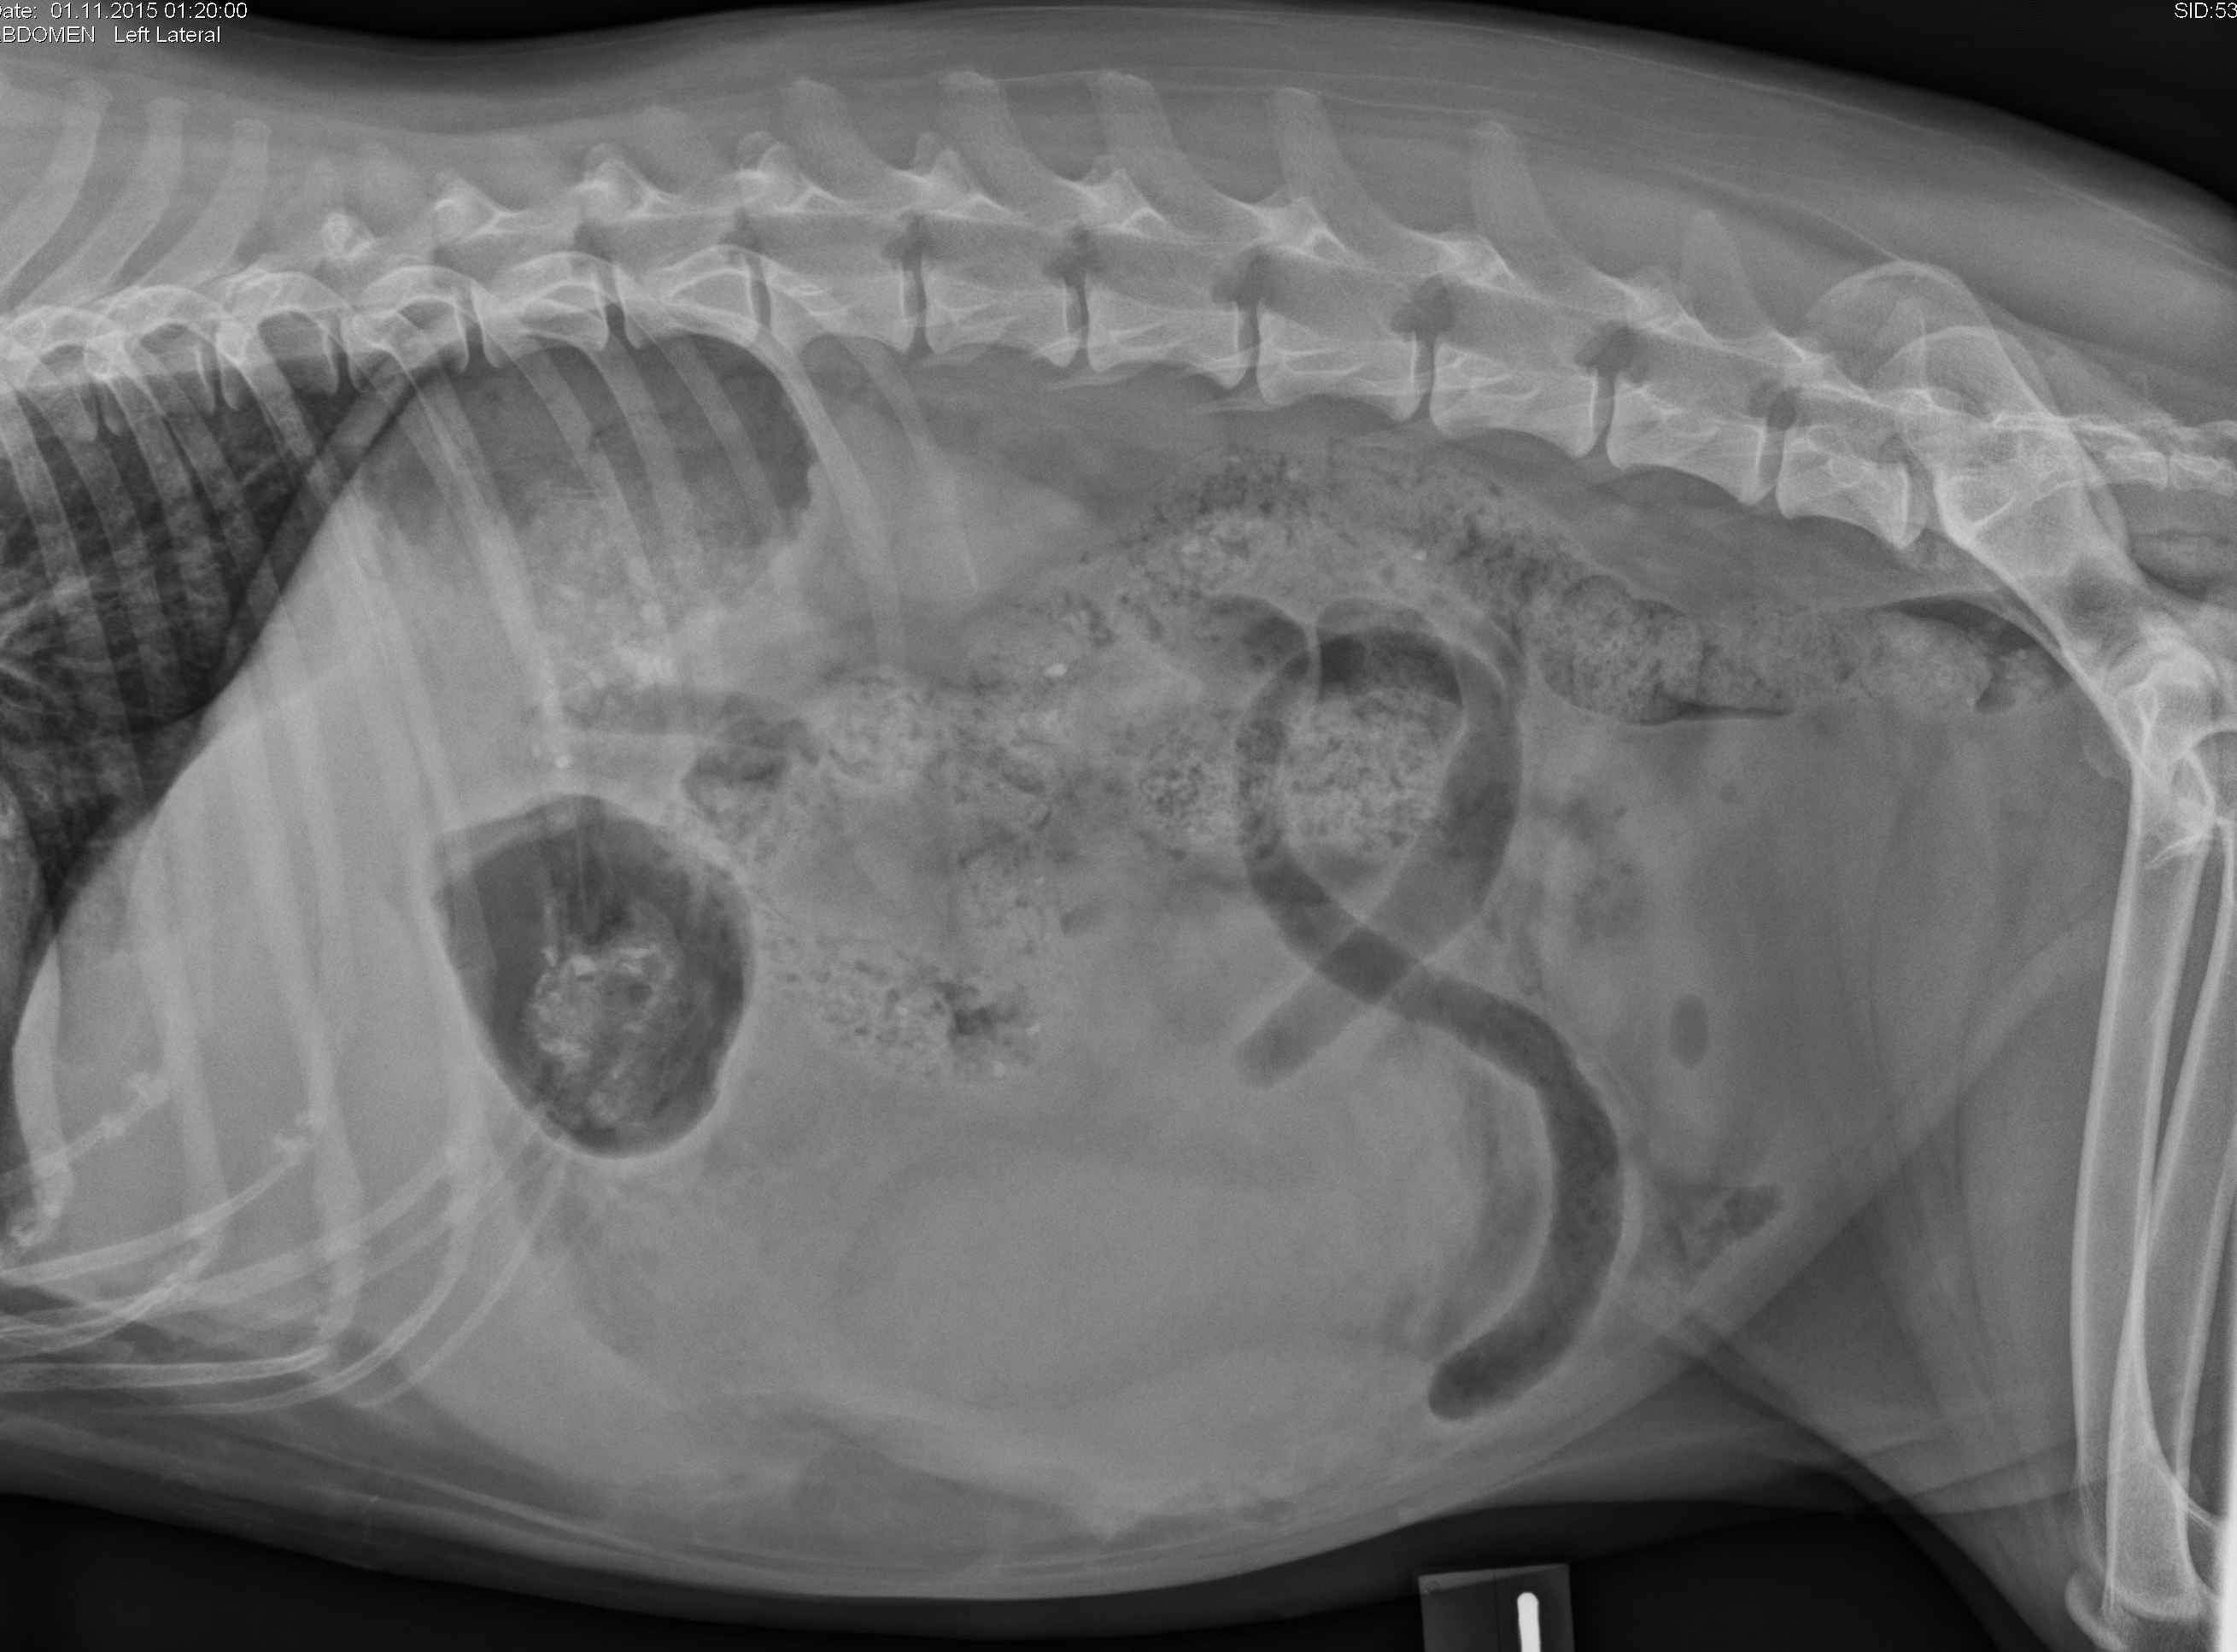

latérale gauche